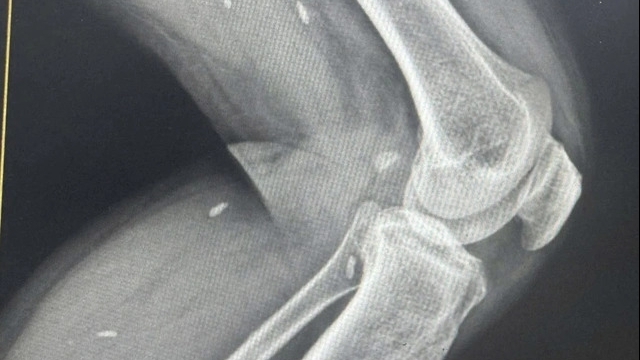

Một trường hợp được xác định viêm cơ tim khi có rối loạn nhịp tim, tăng men tim. Mỗi năm tại Viện vẫn gặp từ vài chục đến 100 trường hợp nghi viêm cơ tim vì rất nhiều trường hợp không thể nuôi cấy và định danh được chính xác loại virus, vi khuẩn bệnh nhân nhiễm.

Theo PGS Hùng, khi bị viêm cơ tim, bệnh sẽ tiến triển rất nhanh. Trước đây khi chưa có hỗ trợ tuần hoàn ngoài cơ thể (ECMO), tỉ lệ tử vong do viêm cơ tim tại Viện Tim mạch quốc gia lên tới 50%. Nhưng hiện tại, nhờ có ECMO, rất nhiều bệnh nhân đã được cứu sống.